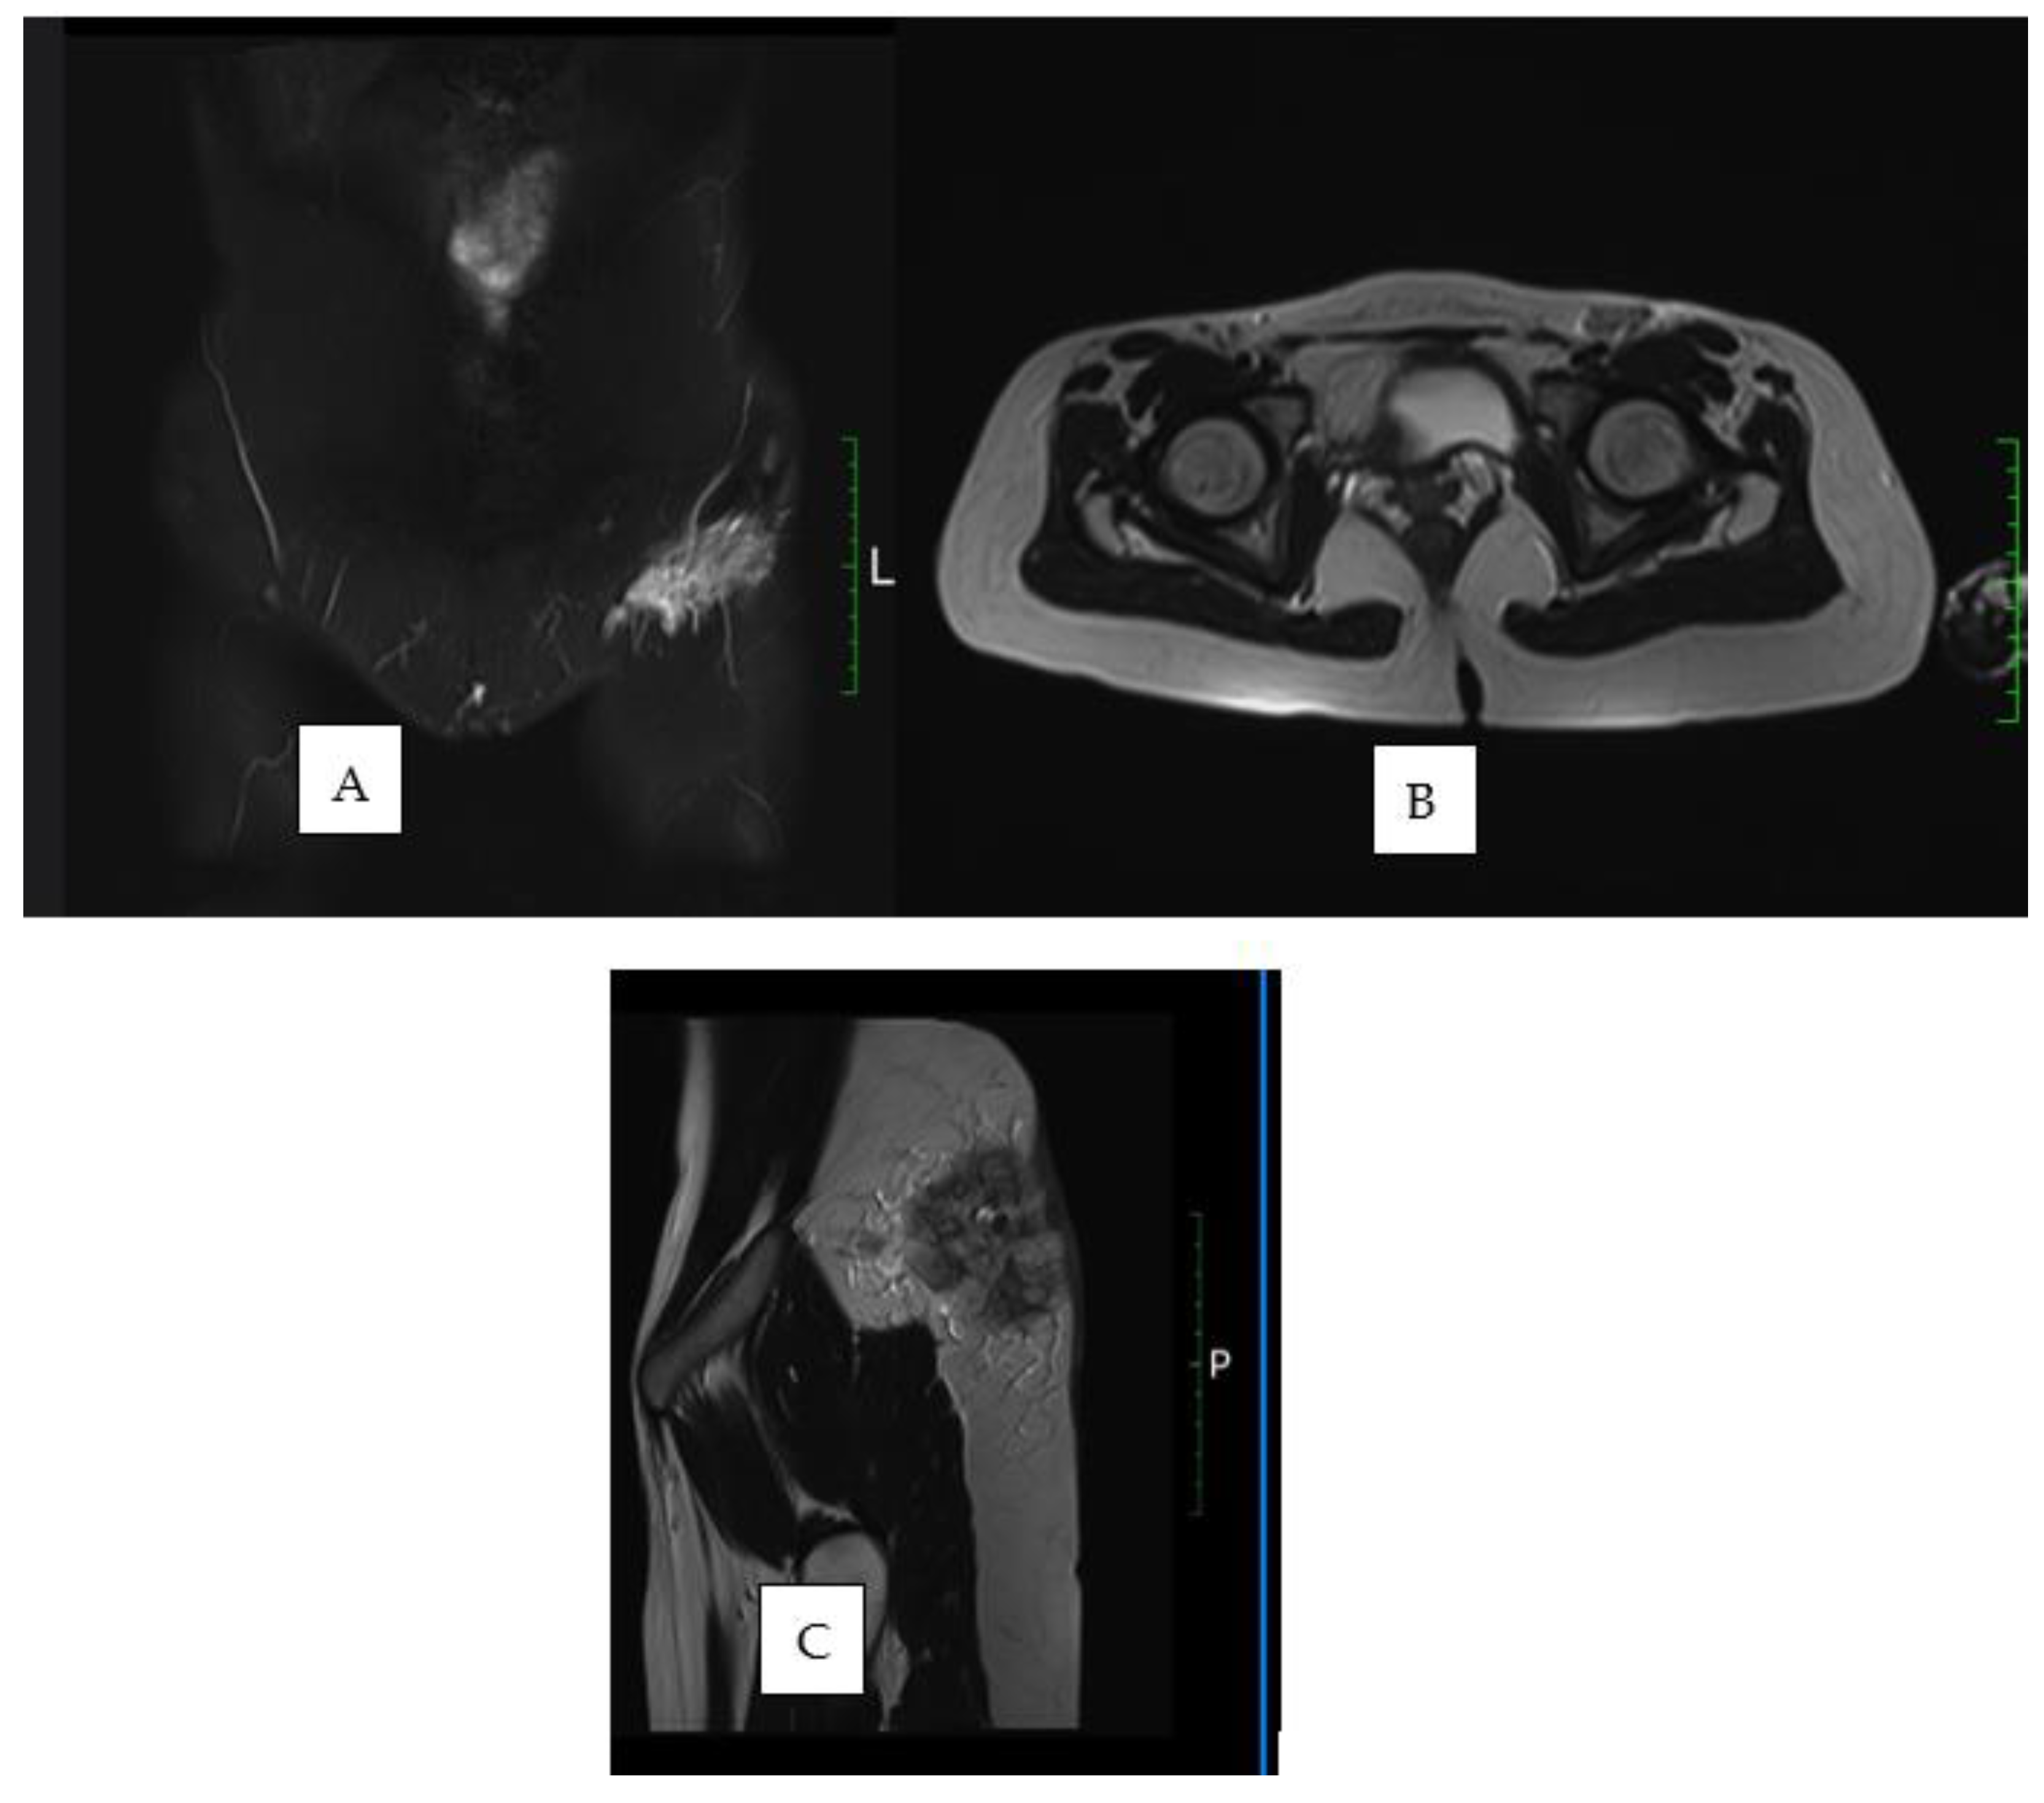

- Kim, J.S.; Jeong, Y.J.; Sohn, M.H.; Jeong, H.J.; Lim, S.T.; Kim, D.W.; Kwak, J.Y.; Yim, C.Y. Usefulness of F-18 FDG PET/CT in subcutaneous panniculitis-like T cell lymphoma: Disease extent and treatment response evaluation. Radiol. Oncol. 2012, 46, 279–283. [Google Scholar] [CrossRef] [PubMed] [PubMed Central]